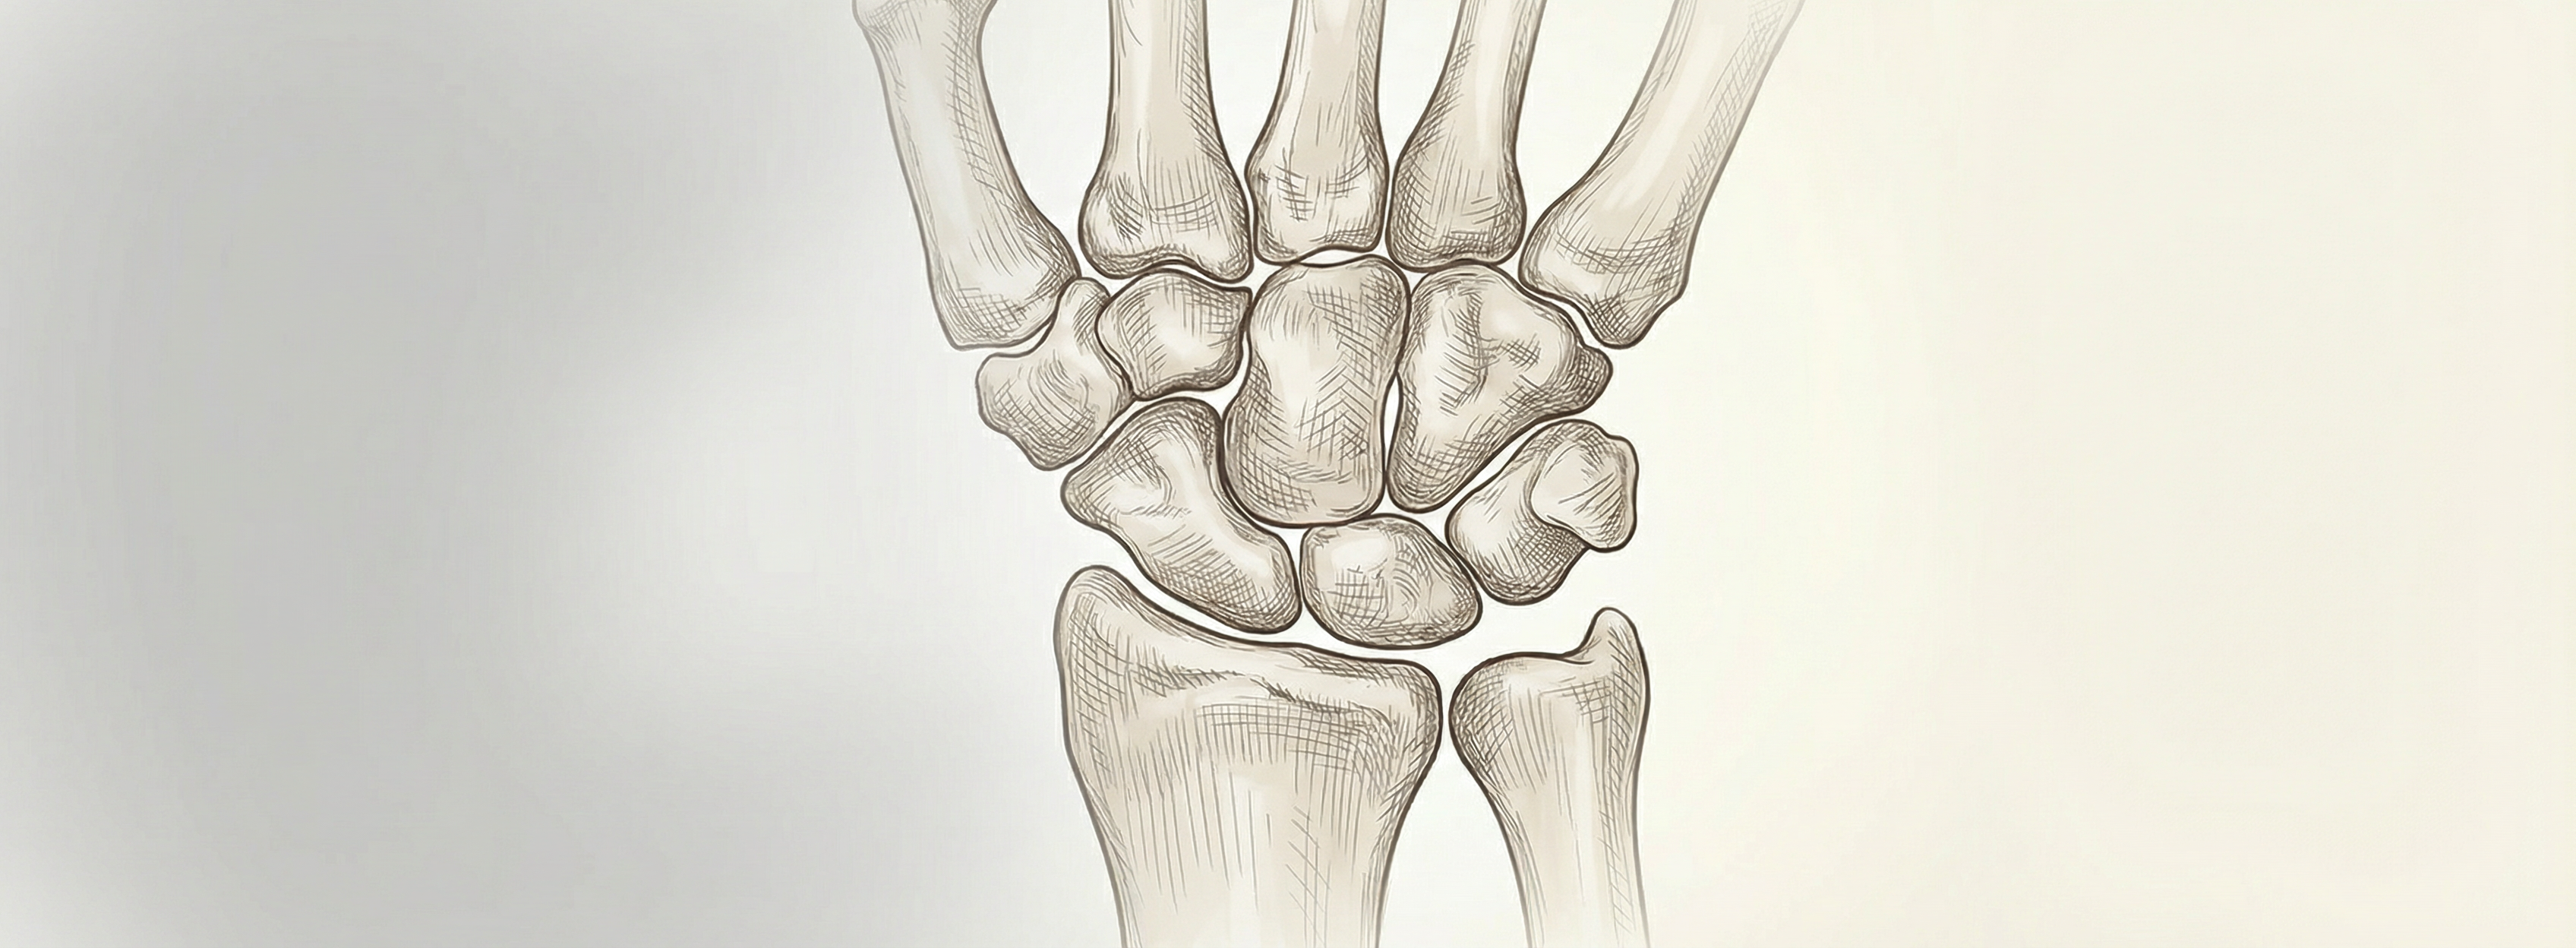

The carpus—eight bones arranged in two rows—forms the mechanical bridge between the forearm and the hand. Understanding their anatomy and biomechanics is essential for accurate diagnosis, rehabilitation, and surgical planning.

The carpal bones are conventionally divided into proximal and distal rows. The proximal row—scaphoid, lunate, triquetrum, and pisiform—articulates with the radius and ulna; the distal row—trapezium, trapezoid, capitate, and hamate—articulates with the metacarpals. Ligamentous and muscular attachments maintain stability while allowing the mobility required for grasp and fine motor tasks.